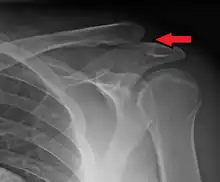

![]() | |

| An Xray showing a separated shoulder. Notice the separation between the end of the collarbone and the scapula. | |

X-ray indicates a separated shoulder when the acromioclavicular joint space is widened (it is normally 5 to 8 mm).[9]